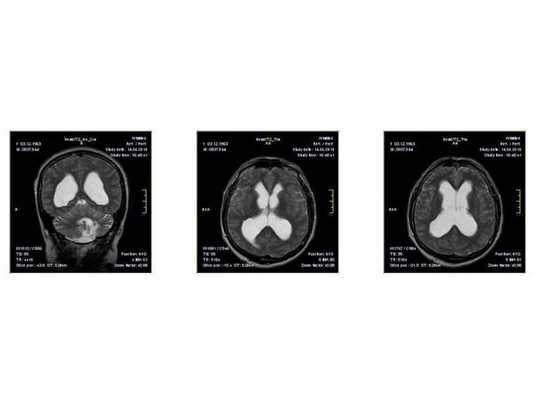

По заключению МРТ от 14.05.2013, после операции в левом полушарии мозжечка появились кистозно-глиозные изменения (на месте повреждённых нейронов образовались рубцовая ткань), а также выраженная внутренняя асимметричная гидроцефалия (избыточное скопление спинномозговой жидкости в полости черепа).

- МРТ в динамике показывает постепенное сужение желудочковой системы на 2 мм. Для сравнения представлены снимки МРТ от 14.05.2013 и от 16.10.2014.